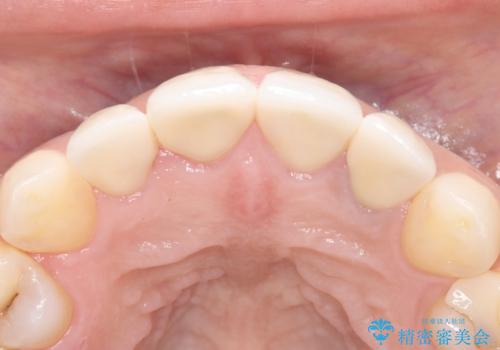

オールセラミックは、光の透過性が天然歯に非常に近いため、周囲の歯と見分けがつかないほどの透明感と自然な色調を再現できます。また、プラークが付着しにくく、金属アレルギーの心配もありません。

緻密な色合わせと形態調整を重ねた結果、長年のコンプレックスであった前歯の欠けや変色が解消。機能性と審美性が完璧に調和した、自信を持って笑える美しい口元を実現することができました。